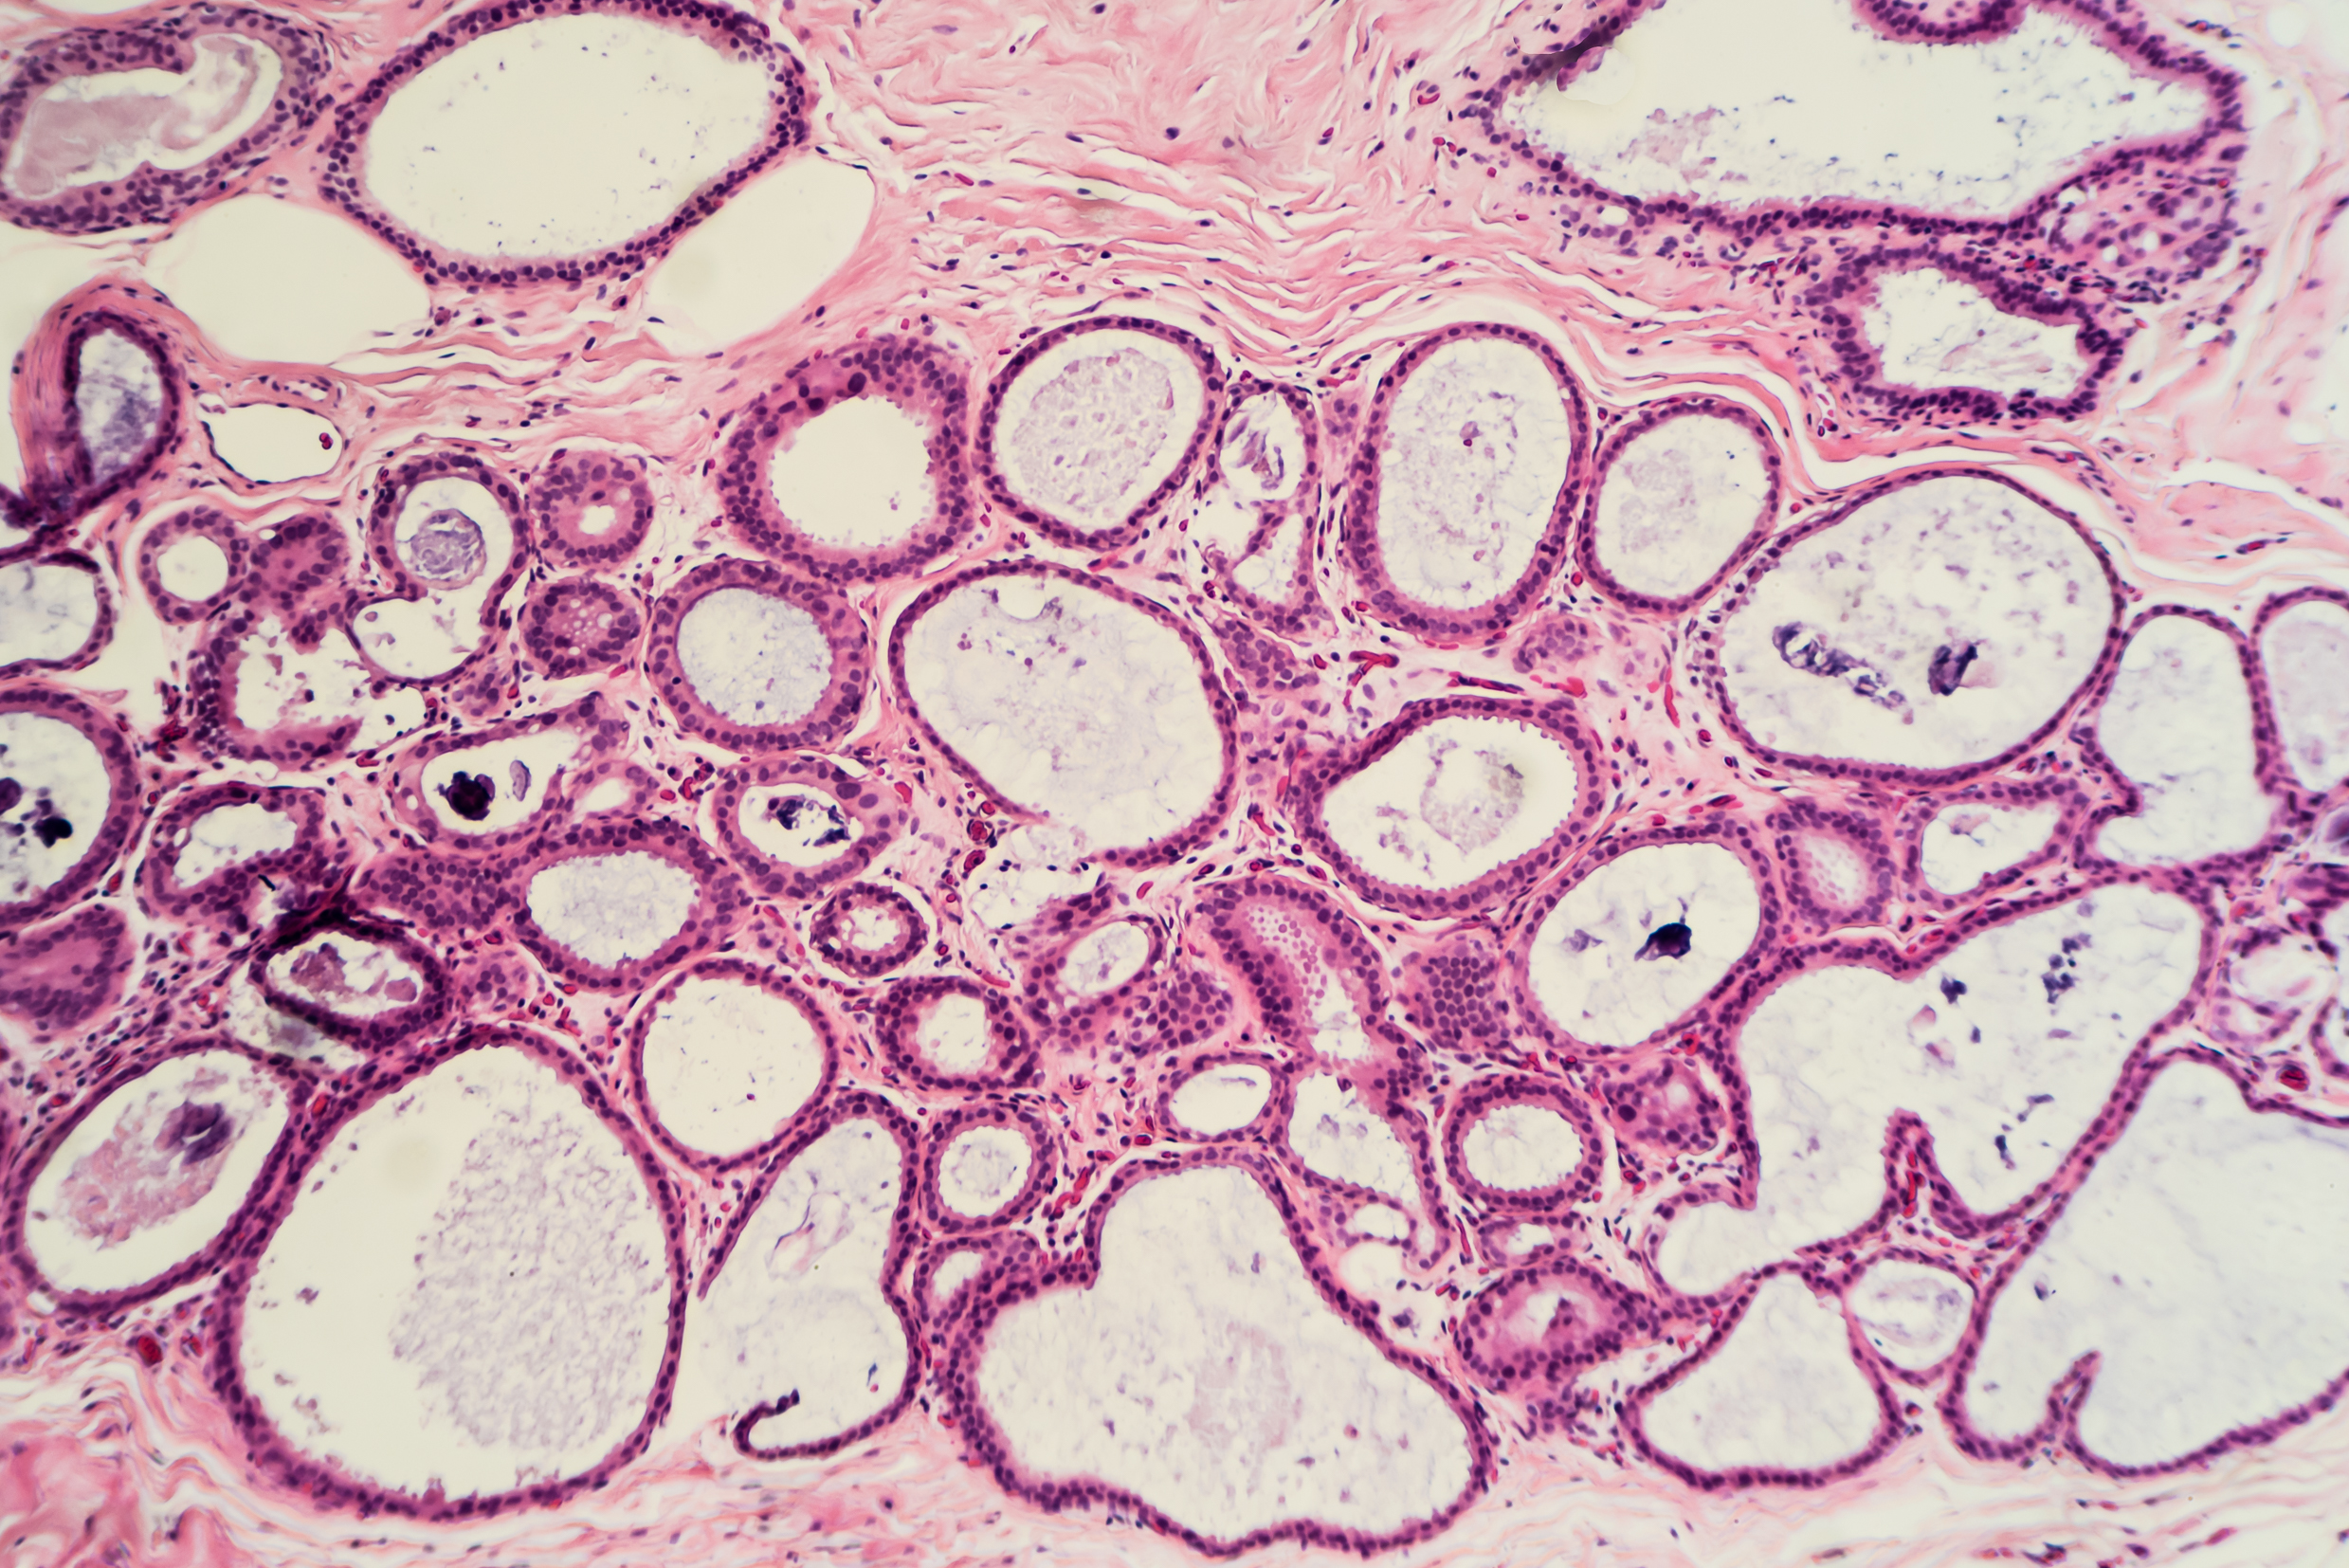

Исследование: микропрепарат молочной железы в медицине

Раздел: Снимки-откровения